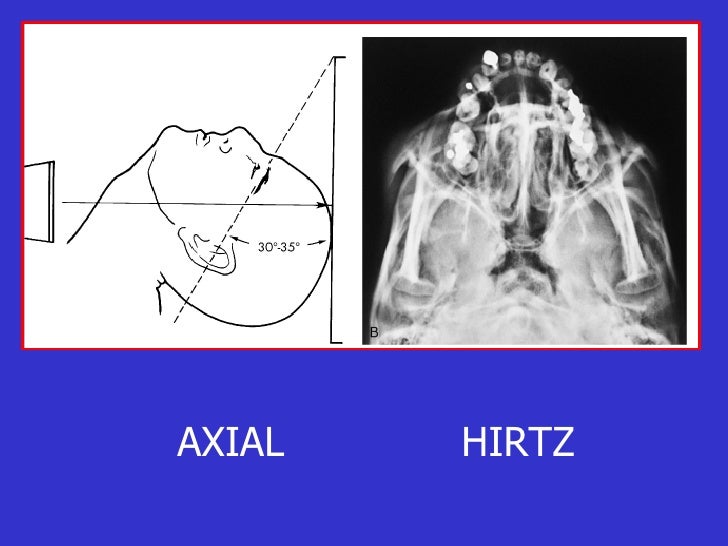

La opción ideal en la sospecha de cualquier traumatismo craneofacial es la TC. En caso de no disponer de tomografía, las proyecciones de radiología convencional más apropiadas en estas situaciones son: el Waters (occipitomental), la proyección de Caldwell (occipitofrontal), la lateral y la proyección de Hirtz o de arcos cigomáticos.

Entre sus principales indicaciones, esta proyección hace posible la evaluación de la parte posterior de la mandíbula, involucrando el tercio posterior del cuerpo mandibular, la zona gonial o angular, la rama ascendente y la zona subcondilar inferior, las cuales se observan sin superposición de otras estructuras óseas. También se puede.

grupos de senos. Proyección PA axial (Método Cadwell): Senos frontales y etmoidales anteriores. Proyección de Waters (Parietoacantial): con boca cerrada: Senos maxilares Proyección de Waters (Parietoacantial) con boca abierta: Senos maxilares y esfenoidales. Proyección Submentovertical: Senos etmoidal y esfenoidal. Centraje: Línea.